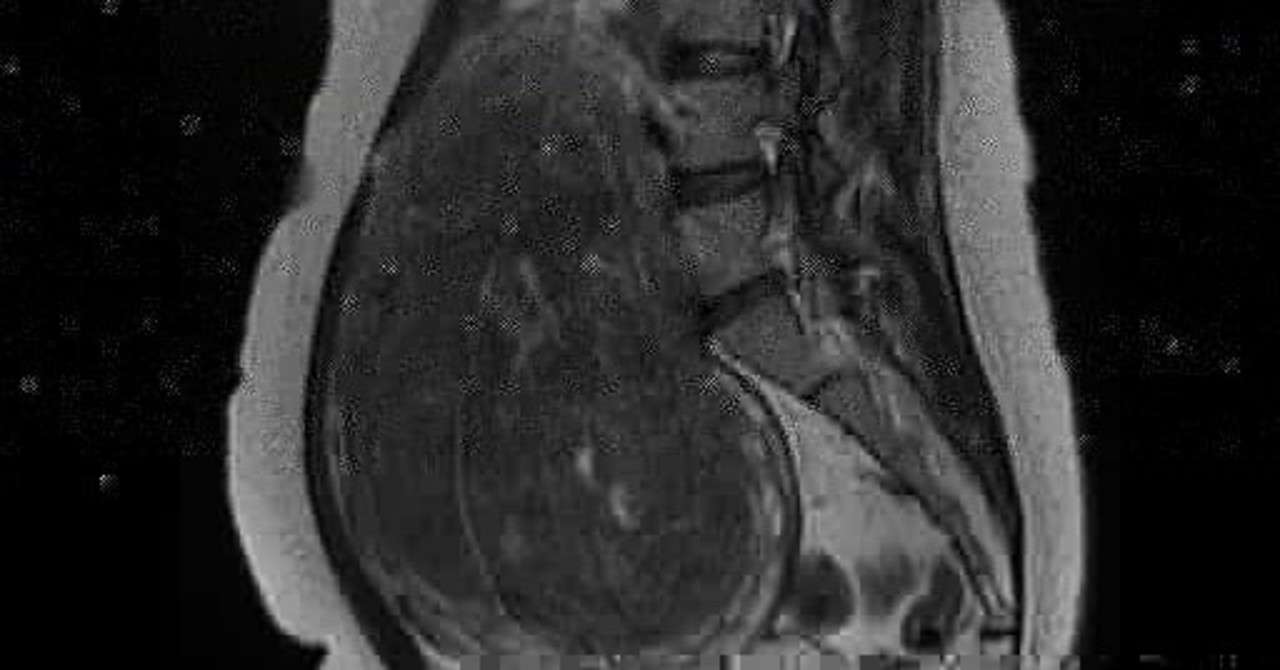

子宮筋腫 Mri画像 Before After 閲覧注意 いやすひと ヒカル 癒しと気づきが 必要なタイミングで届きます

Mri画像と病院探し 彡 子宮筋腫 激痛とのタタカイ 楽天ブログ

私の巨大子宮筋腫 Mri筋腫画像あり 妊娠6ヶ月で死産した天使ママ 第二子妊娠中